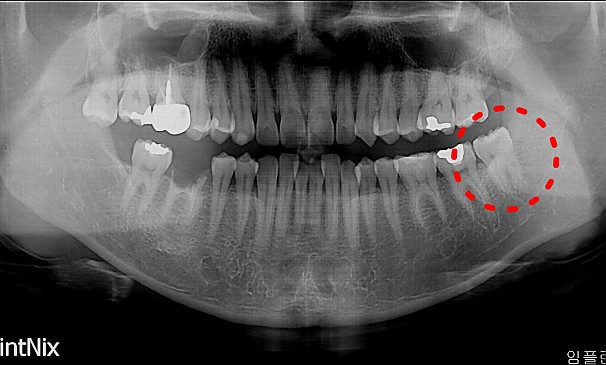

자가치아이식술

김OO님 전후사진 | 치료 기간 : 1주

치료 전

치료 후